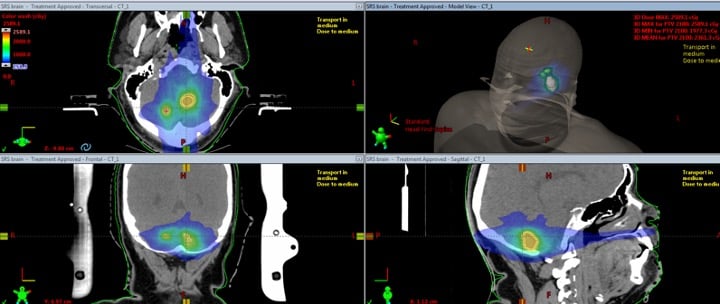

Figure 1: CT image of lesions in different planes.

There have been several cases where the angular independence of the device has been helpful in catching multiple lesions on the same plane. For instance, with one particular case, the lesions from the anterior and posterior positions were not in the same plane. One lesion was oversized, while the other was not. In this case, I created a QA plan using SRS MapCHECK. With that plan stored in the system, it was obvious rotation was needed to catch both lesions optimally on the device. When adding the rotational component within the software and delivering the plan, using criteria of 2% dose difference and distance of 1 millimeter, the plan had an excellent passing rate of 97.9.

Another case that stood out was when the SRS MapCHECK detected two prominent lesions and the beginning of a third lesion. In this instance, I took a second scan with SRS MapCHECK to more accurately target the third lesion. This example really demonstrates the highly accurate measurements capable with the device, even in the gradient fall-off region. Catching a gradient dose delivery to an off-plane lesion is just as difficult, if not more so, than catching one in plane, and the SRS MapCHECK does both well.